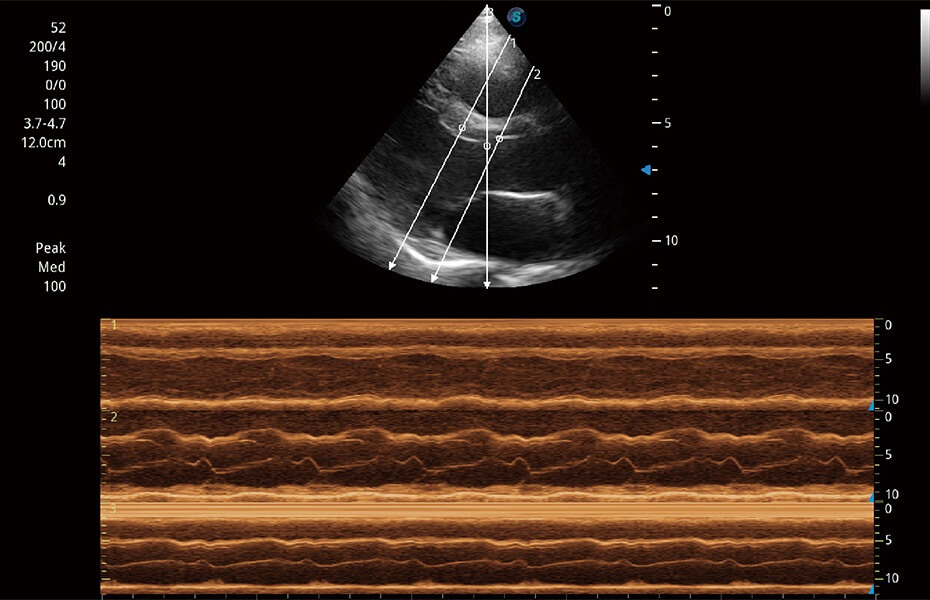

ProPet 60 作為一款高端臺式動物超聲設備,為動物醫(yī)生的日常診斷提供了一系列貼合動物臨床需求、解決臨床實際問題的高級成像功能。憑借全系列高清探頭,滿足醫(yī)生對腹部、心臟、生殖、淺表、肌骨等成像的所有需求,切實幫助您提升檢查效率,提高診斷信心。

動物是人類最親密的朋友和最值得信賴的伙伴。開立醫(yī)療也一直致力于探索動物專用的超聲影像解決方案。 全新推出的ProPet系列,是開立在動物超聲影像智能化、專業(yè)化、精準化的一次跨越式革新。動物不能用言語來表述自己的不適,通過超聲影像,ProPet系列搭建了動物醫(yī)生與不同物種溝通的“橋梁”,為動物醫(yī)生注入了“治愈之力”。